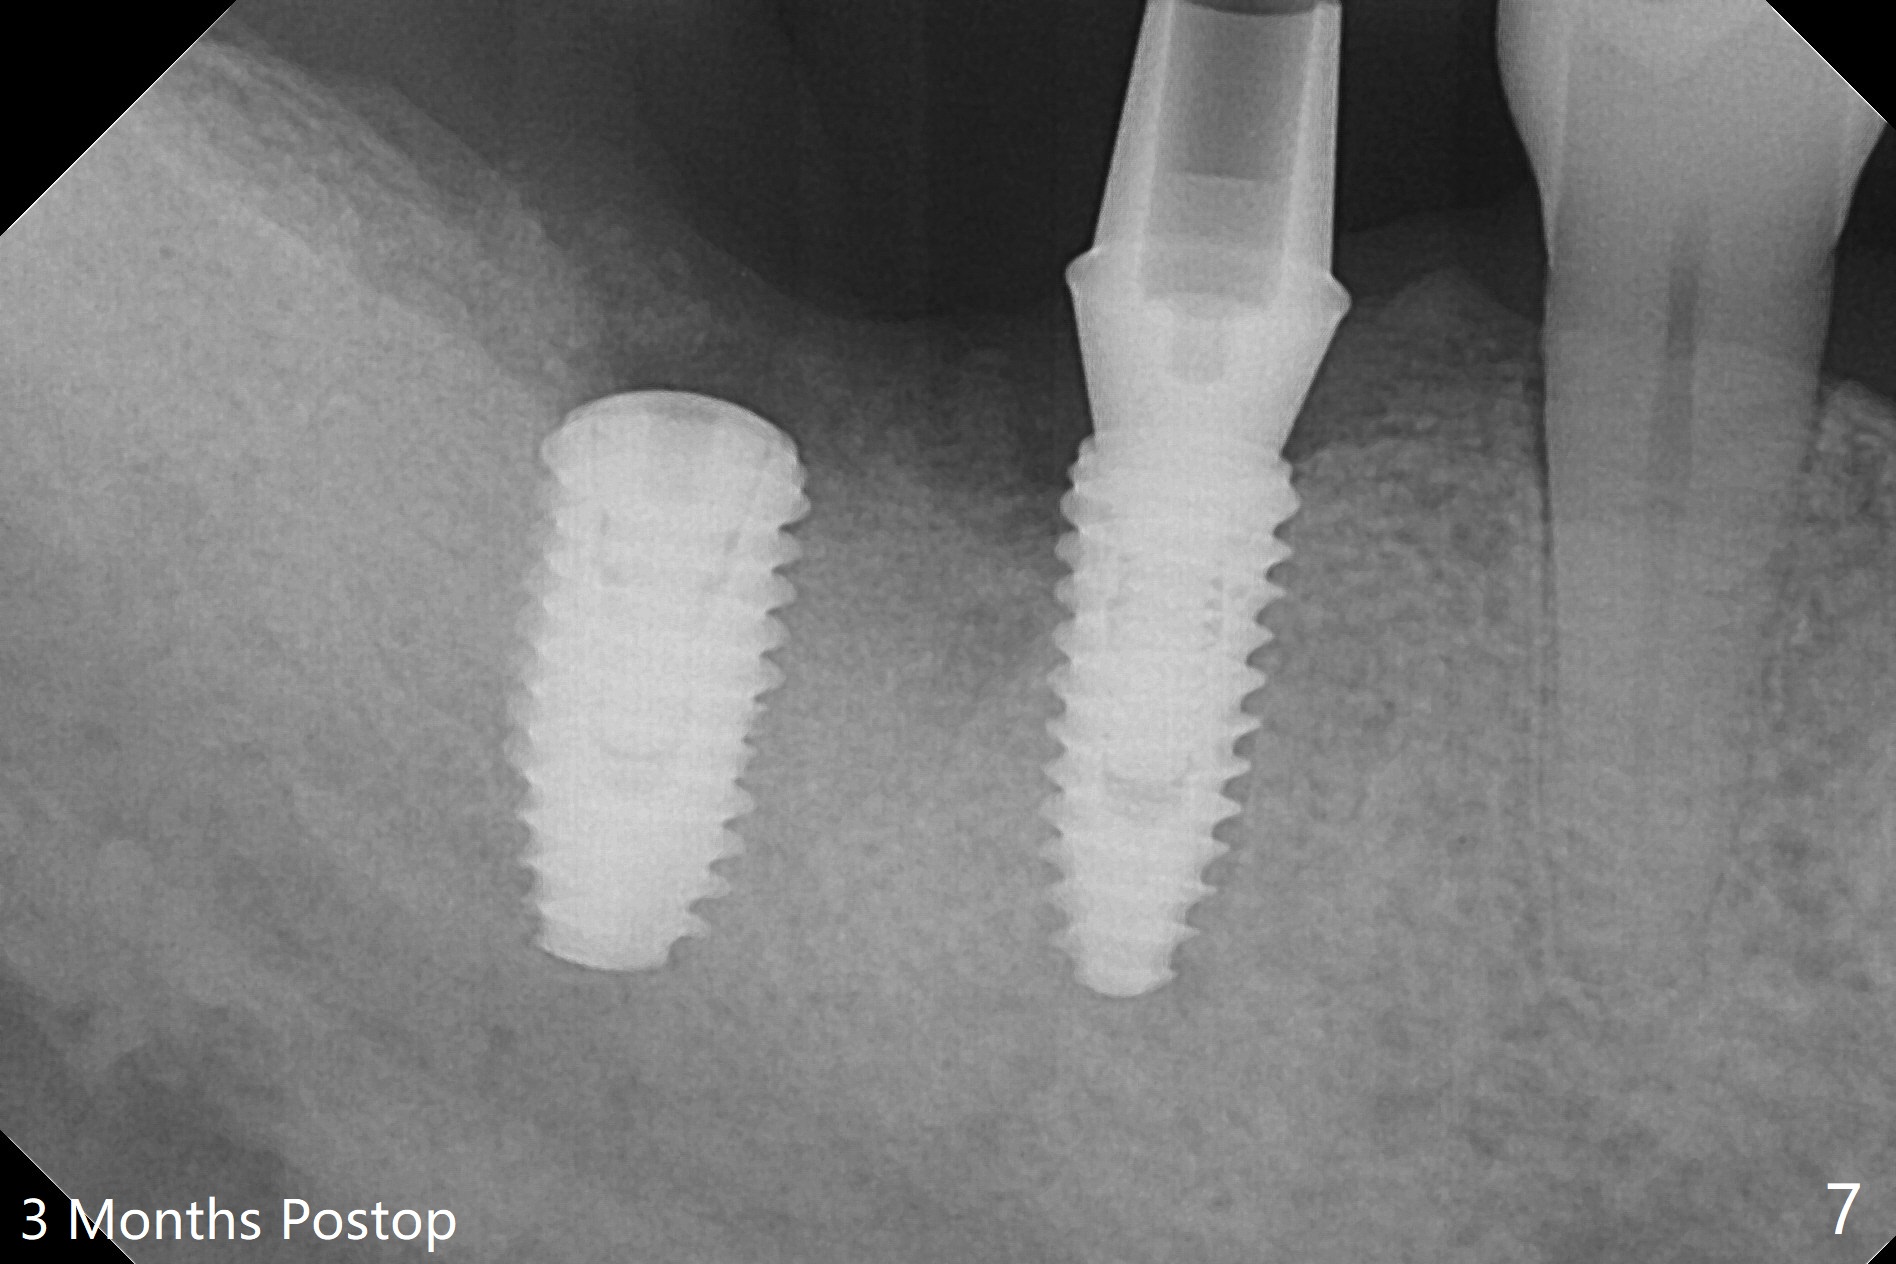

Osteotomy at the sites of #30 and 31 is initiated with Magic Split, followed by Magic Expanders (3.0 and 3.8 mm) at #31.  Initial depth of osteotomy is 13 mm with 2.2 mm drill (Fig.1).  After adjustment of the trajectory at #31 (Fig.1 arrow) and deepening the osteotomy by 2 mm, dummy implants are placed with stability (Fig.2).  Following increase in osteotomy at #31, the larger implant in fact loses stability (Fig.3).  The loose implant is pushed distal (Fig.4 arrow) with placement of autogenous bone mesial (*).  The stable implant at #30 (Fig.3) and its abutment (Fig.4) are used as a post to hold periodontal dressing, which covers the wound at #31 after placement of collagen plug and suturing.  In fact the same technique could be used when socket preservation was performed if an implant were placed at #30 at the same time.  When the periodontal dressing dislodges, the wound at #31 heals uneventfully (Fig.5,6).  The bone graft seems to remain in place 3 months postop (Fig.7).  The implant is uncovered with placement of a 6.8x7 mm healing abutment 4 months postop.  When a cementation abutment is placed and prepped, the buccal margin is much lower than the lingual (Fig.8 taken prior to cementation).  The patient enjoys mastication with the new implant crowns 3.5 months post cementation (Fig.9).